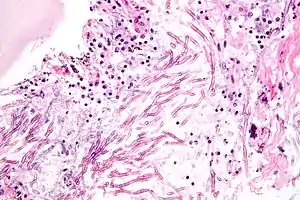

| H&E stain showing a fungal pneumonia (pulmonary aspergillosis) | |